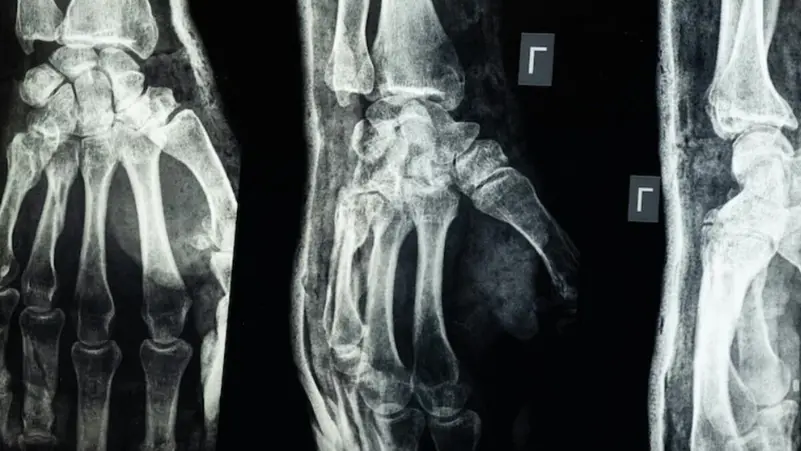

أعلن فريق بحثي في مقاطعة تشيجيانغ شرق الصين عن ابتكار طبي جديد يتمثل في “غراء عظمي” قادر على معالجة الكسور وتركيب الشظايا العظمية خلال ثلاث دقائق فقط، في خطوة وُصفت بأنها اختراق علمي في عالم جراحة العظام، بحسب ما نقل موقع “إن دي تي في” NDTV.

وأكدت الاختبارات المعملية أن Bone-02 نجح في تحقيق نتائج جيدة من حيث السلامة والفعالية. وفي إحدى التجارب، أُجريت العملية في أقل من 180 ثانية (ثلاث دقائق)، بينما كانت طرق العلاج التقليدية تتطلب وقتاً طويلاً لزرع صفائح فولاذية ومسامير.

وبحسب الاختبارات المعملية، تمكن الغراء من تحقيق قوة ربط تفوق 400 رطل، وقوة قص تبلغ نحو 0.5 ميغاباسكال، وقوة ضغط تقارب 10 ميغاباسكال. كما أظهرت التجارب على أكثر من 150 مريضاً نتائج ناجحة، ما يعزز احتمالية أن يصبح بديلاً للزراعات المعدنية التقليدية التي تُستخدم في تثبيت العظام. كما يقول العلماء إنه قد يقلل أيضًا من مخاطر العدوى.